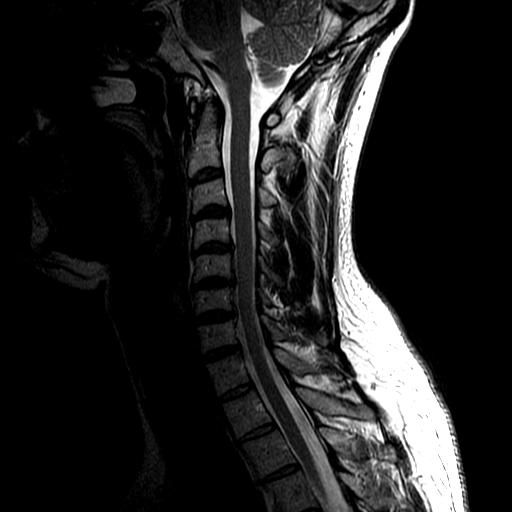

Bad pic of the one of the MRI but c4/5 disc ruptured and c7

Jeebus. That picture.  That looks nasty. My aunt had what I would assume would be a similar operation after a major car accident. She had a broken neck - an incomplete fracture between the vertebra called C1 and C2, the top of the spinal column, which holds the skull on the neck (you're probably aware of all those Cs) - all that stopped it from being a complete internal decapitation was 1 mm of tissue, holding her head onto her neck. She spent months at GF Strong in Vancouver, for rehab.

OK, this is just dumbass me. Is the problem with the three vertabrae closest to the throat area that appear to be separated?

Cripes, disc material appears to have spread out and down the back of the vertebrae impinging upon the spinal cord (from that one bad pic, need to see the rest of the series to be sure). No wonder you were in so much pain. I wonder if they talked to you about what to do with the set of your cervical spine after your surgery because I see disc bulges throughout your c-spine that need attention before they rupture as well.